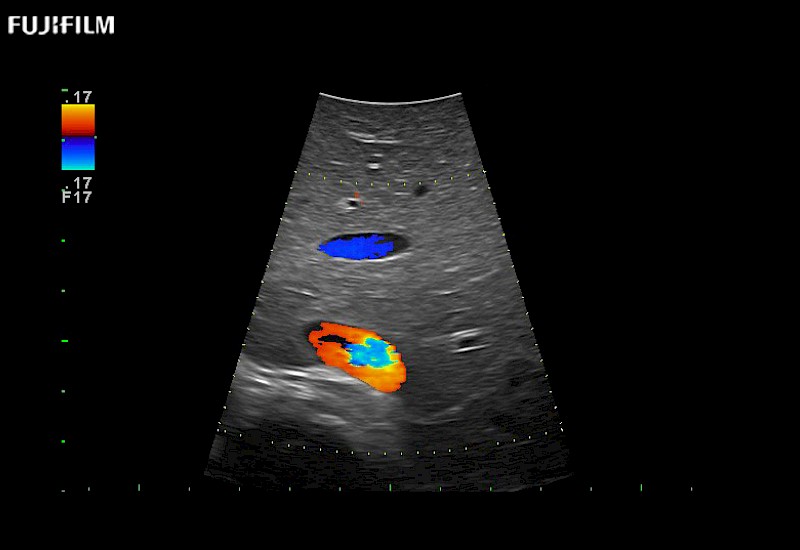

Extraordinary high-resolution digital imaging

Exceptional transducers

for use during open and laparoscopic procedures: Tumor localization & staging, Ablation, Resection, Biopsy, Transplant, Abdominal exploration, Robotic surgery

Multi-Parametric imaging modalities